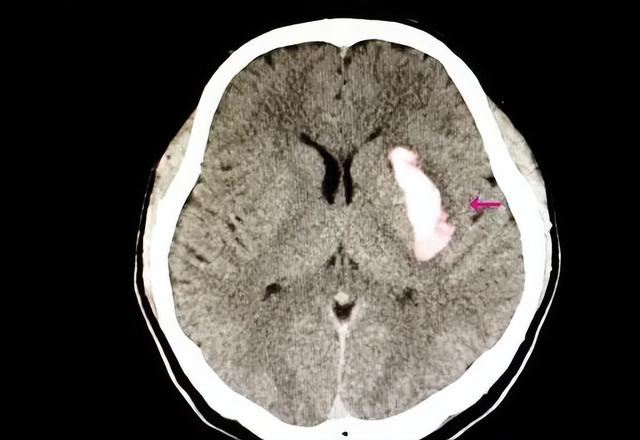

长期高血压得不到控制 , 会导致很多严重的并发症 。 它是很多脑出血发生的主要诱因 , 对患者的生命安全造成了巨大的威胁 。

脑出血 , 也被称为脑溢血 , 是一种非常严重的脑血管疾病 。 它通常是由于脑实质内部的血管发生破裂所引起的 。

这种破裂往往不是由外伤引起的 , 而是由于高血压所导致的小动脉硬化破裂 。 高血压实际上是导致脑出血最常见的因素之一 。 超过一半的脑出血病例都与高血压有关 。

人体的脑血管壁原本就很薄 , 而对于高血压患者来说 , 其脑血管壁更是变得异常脆弱 。 当血压突然升高时 , 这些薄弱的血管就可能破裂 , 引发脑出血 。